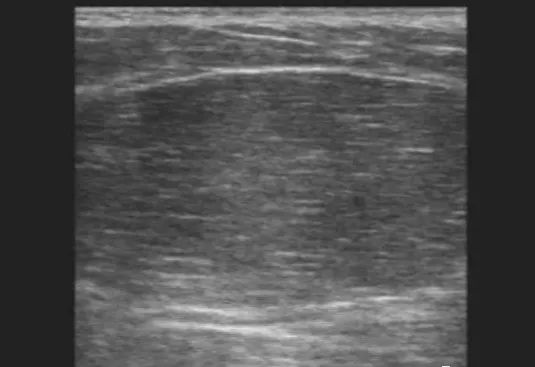

4. 腋下脂肪瘤:超声表现为浅筋膜层见椭圆形肿物,长轴与皮肤平行,内部回声为等回声及强回声,并可见带状或羽毛状强回声,内部一般未见血流信号。